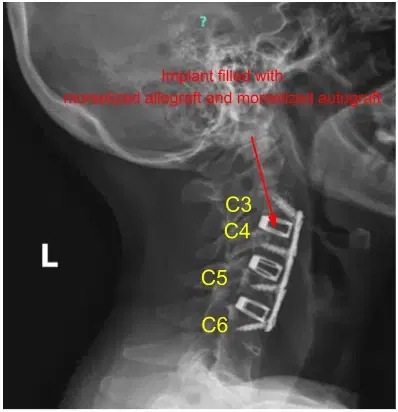

Epidural bleeding was controlled easily with Surgiflo and gentle cotton tamponade. We then trial-sized our implant and obtained x-rays. We filled our implant with a morselized allograft and morselized autograft.

Epidural bleeding was controlled easily with Surgiflo and gentle cotton tamponade. We squared out the disc space with the high-speed drill and prepared the disc space for arthrodesis. We then trial-sized our implant and obtained x-rays. We filled our implant with morselized allograft and morselized autograft.

We measured out our anterior plate, placed it over our levels of interest, and pinned it into place. We obtained x-rays, and then applied the screws as listed above. We locked all the screws in place and obtained final AP and lateral x-rays.

The patient made a full recovery and continued to take part in regular daily activities. A postoperative cervical spine 2 or 3 view x-ray was ordered and the sagittal view is shown below.